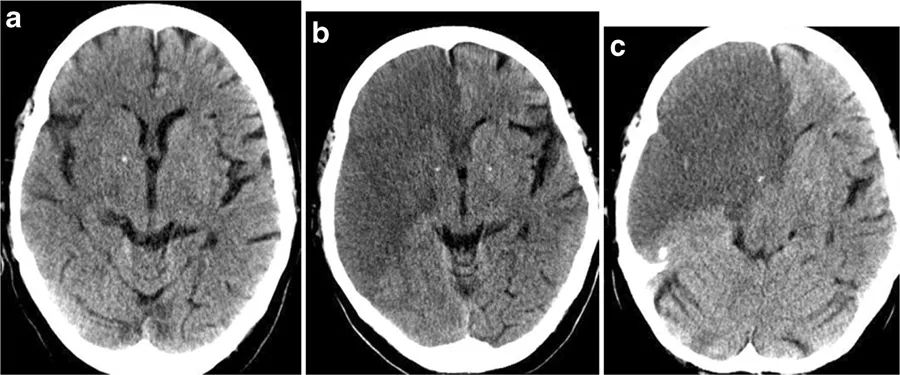

图2 恶性脑梗死的进展过程。在卒中发病的6小时内,CT仅显示额叶、岛叶皮质、颞叶、尾状核和豆状核的轻度密度减低(左);12小时后,可见大脑中动脉和大脑前动脉供血区域边界清晰的梗死区域(中);但没有占位效应。24小时后,病灶出现占位效应,中线移位(右)。